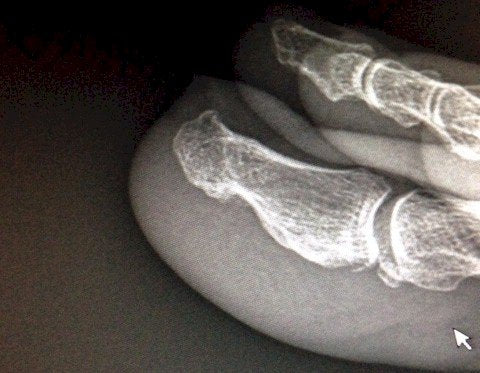

A subungual exostosis is a bone spur that forms beneath the great toe nail. The spur is found equally in men and women and usually presents with an onset between the ages of 30 and 50 years of age. Diagnosis is made with a lateral x-ray of the foot that shows a pronounced bone spur on the dorsal, distal tip of the distal phalanx of the great toe.